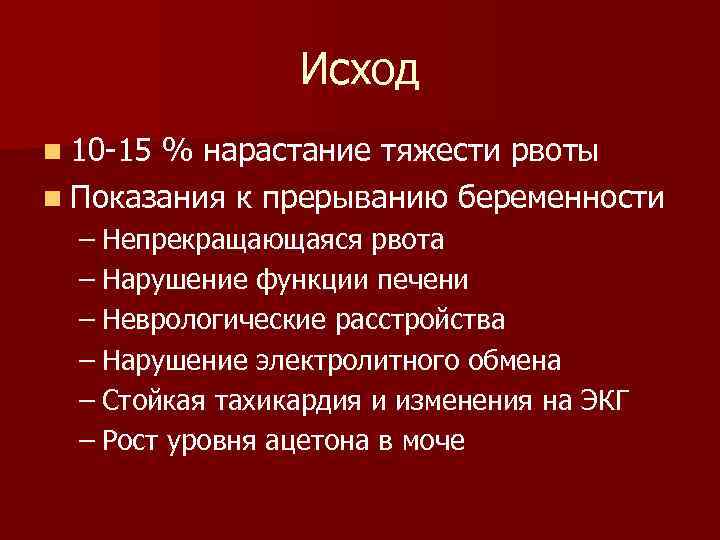

Исход n 10 -15 % нарастание тяжести рвоты n Показания к прерыванию беременности – Непрекращающаяся рвота – Нарушение функции печени – Неврологические расстройства – Нарушение электролитного обмена – Стойкая тахикардия и изменения на ЭКГ – Рост уровня ацетона в моче

Исход n 10 -15 % нарастание тяжести рвоты n Показания к прерыванию беременности – Непрекращающаяся рвота – Нарушение функции печени – Неврологические расстройства – Нарушение электролитного обмена – Стойкая тахикардия и изменения на ЭКГ – Рост уровня ацетона в моче